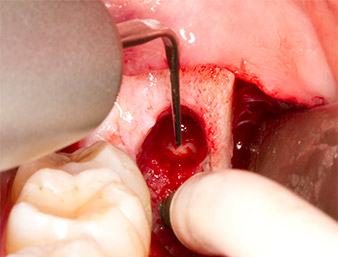

À l'aide d’un insert pour le débridement parodontal (Piezomed P1), l’espace ligamentaire parodontal de la racine résiduelle est ensuite élargi de manière minimale (Fig. 8).

Le même insert activé est inséré dans le canal radiculaire et détache le fragment sous l’effet de ses vibrations à micro-oscillations (Fig. 9, 10).

Il est ensuite possible, grâce à l’insert P1, d’extraire en un seul geste le reste radiculaire d’environ six millimètres de long (Fig. 11).